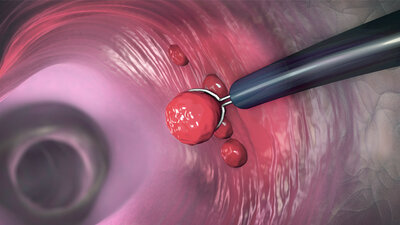

• Diagnostische Punktionen zur Gewebeprobenentnahme Um eine Krankheit sicher zu diagnostizieren – oder auch, um sie auszuschließen – ist es oft unabdingbar, Gewebeproben aus den entsprechenden Organen im Labor zu untersuchen. Dies gilt insbesondere, wenn der Arzt den Verdacht hat, dass sein Patient an Krebs leidet. Aber auch bei vielen anderen Erkrankungen sind solche Biopsien wichtig.

Eine für den Patienten relativ verträgliche Methode, Gewebeproben zu gewinnen, ist die Feinnadelpunktion. Mit Hilfe einer Spezialspritze und einer sehr dünnen Hohlnadel entnimmt der Arzt dabei Zellen und Gewebe, beispielsweise aus der Schilddrüse (Schilddrüsenpunktion) oder der weiblichen Brust (Brustpunktion).

Auch bei der Stanzbiopsie handelt es sich um eine Punktion. Die Hohlnadel ist allerdings deutlich dicker und wird mit oft hoher Geschwindigkeit in die verdächtige Region "geschossen". Solche Stanzbiopsien setzten Ärzte zum Beispiel bei einer Untersuchung der Vorsteherdrüse bei Verdacht auf Prostatakrebs ein, oder auch bei einer Knochenmarkspunktion (hier ohne hohe Geschwindigkeit).